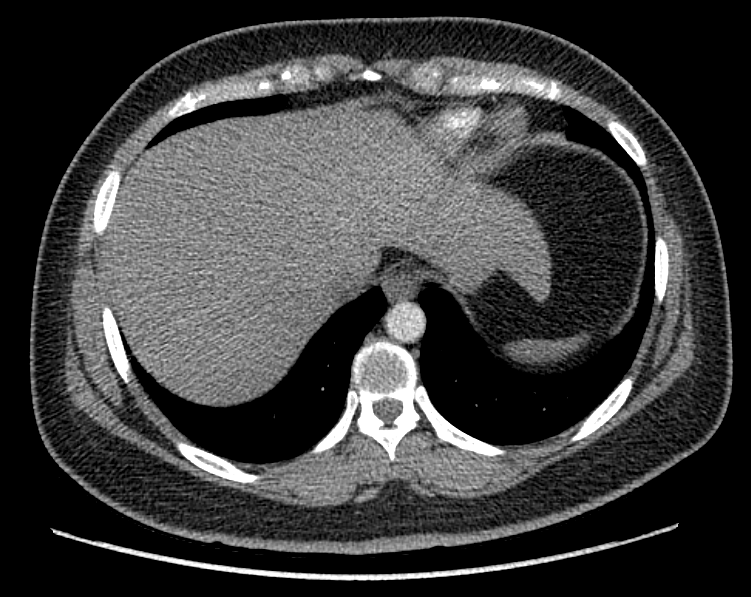

F/34

°Ç°­°ËÁø»ó ½ÃÇàÇÑ Chest PA »ó mediastinal widening ¼Ò°ßÀ¸·Î further evaluation À§ÇØ ³»¿øÇÔ.

Áõ»óÈ£¼Ò ¾øÀ¸¸ç ½Åü°ËÁø»ó ƯÀÌ¼Ò°ß ¾øÀ½.